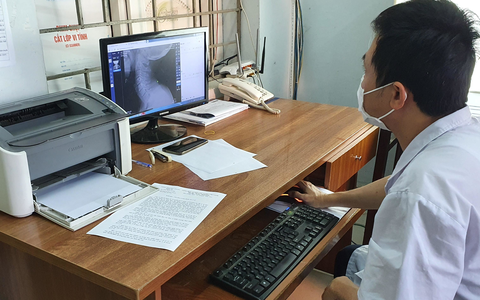

Sản phẩm DrAid™ của VinBrain vừa chính thức được Cơ quan Quản lý Thực phẩm và Dược phẩm Hoa Kỳ (FDA) ra công văn chấp thuận.

Nếu vượt qua những bài kiểm tra khắt khe từ FINDDX, Tổ chức y tế thế giới (WHO) sẽ chứng thực sản phẩm DrAid™ của VinBrain được phép ứng dụng trên phạm vi toàn cầu.

DrAid - phần mềm chẩn đoán hình ảnh y tế do VinBrain (Tập đoàn Vingroup) nghiên cứu, phát triển dựa trên bộ dữ liệu lớn nhất Việt Nam gồm 1,3 triệu hình ảnh X-quang với sự tham gia của gần 1.000 bác sĩ tại hơn 100 bệnh viện.